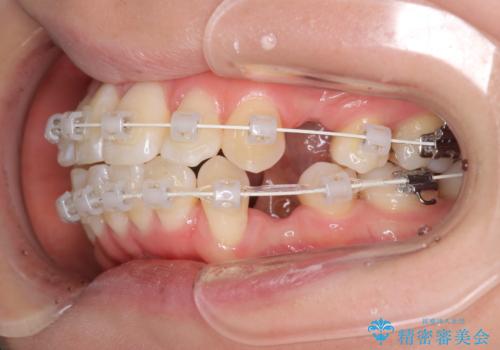

- 審美装置

- 出っぱによる口元の閉じにくさを主訴に来院されました。上顎の出っ歯と上下顎叢生も認められたため、上下顎両側4番抜歯を行い、ワイヤー矯正で治療する治療計画を立てました。

上顎にはMI(マイクロインプラント)を埋入して固定源とすることで出っ歯の改善を図りました。

少しスペースクローズに時間がかかりましたが、MIを用いたワイヤー矯正で

主訴である出っ歯と叢生が改善されました。口も閉じやすくなり、スッキリとした口元になりました。